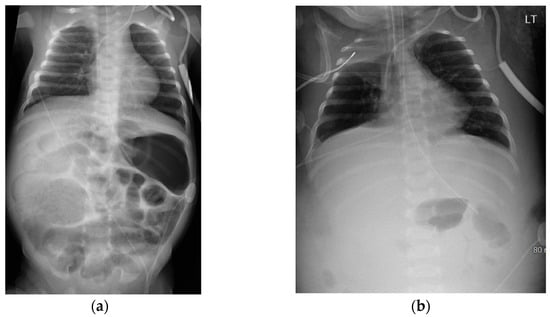

A 36-week female infant was born to a 23-year-old mother via vaginal delivery after induction of labor due to intrauterine growth restriction (11th percentile) and elevated Dopplers. Prenatal care was adequate, with antenatal ultrasounds revealing fetal gastroschisis. The infant’s APGAR scores at 1 and 5 min were 8 and 9, respectively, with routine care initiated upon birth. On examination, the infant had a very narrow gastroschisis defect with an extrusion of a short loop of intestine (Figure 1).

Figure 1. Admission examination showing vanishing gastroschisis.